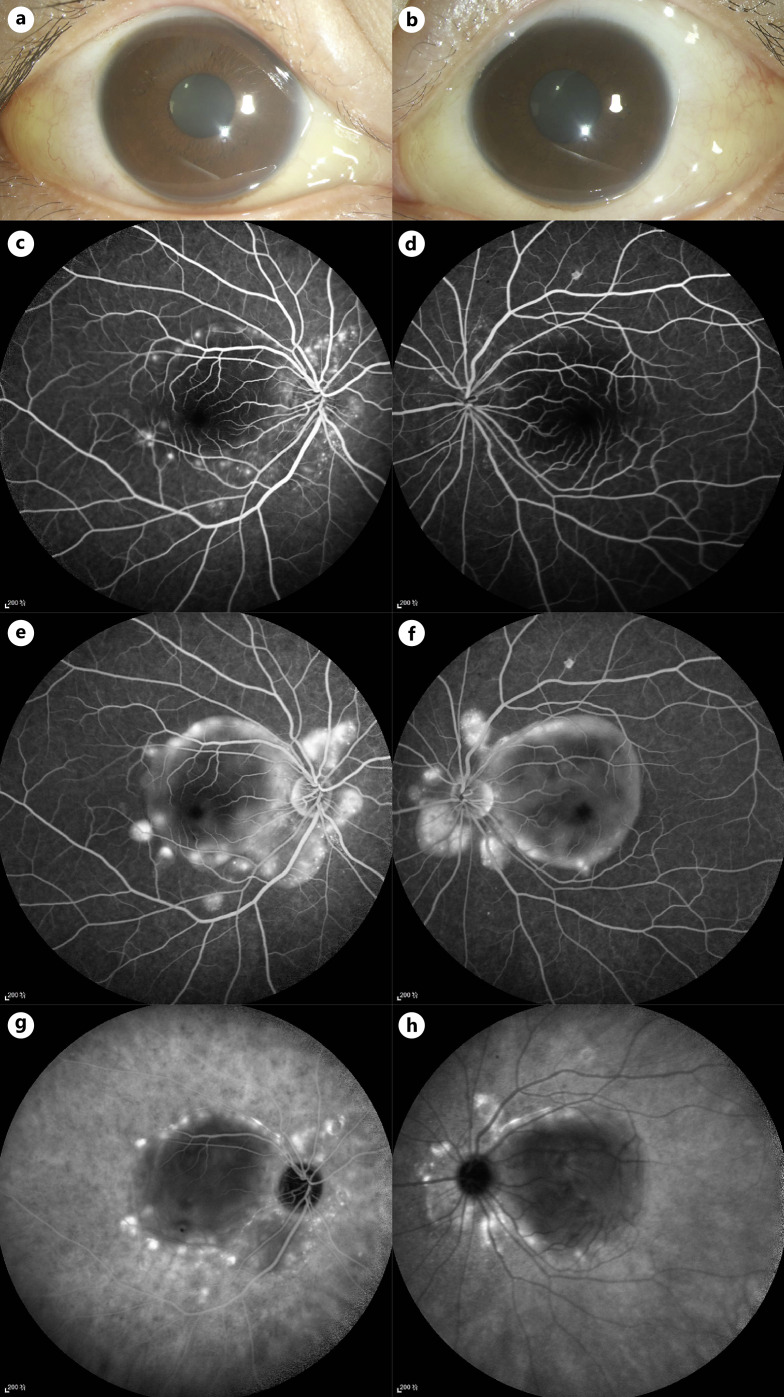

浆液性视网膜脱离(SRD)有多种病因,低白蛋白血症是其中一种罕见的病因。我们报告一例双侧SRD归因于血清白蛋白水平下降引起的系统性红斑狼疮(SLE)。病例介绍:28岁女性,无明显既往病史,双侧眼睑水肿10天,视力模糊3天。光学相干断层扫描显示双眼视网膜下积液;荧光素血管造影显示多个高荧光斑点,伴晚期渗漏和池化。广泛的血清学和全身检查显示血清白蛋白水平轻微下降,无其他明显异常。由于怀疑诊断为Vogt-Koyanagi-Harada病,患者接受了大剂量静脉注射皮质类固醇治疗,但没有任何改善。然而,在白蛋白补充和皮质类固醇剂量逐渐减少后,取得了显著的临床改善。该患者的白蛋白水平下降最终被发现是由于SLE引起的蛋白质丢失性肠病(PLE)。结论:该病例是一种罕见的双侧SRD伴slee相关PLE所致低白蛋白血症的病例。报告显示,眼部受累,如眼睑水肿和SRD可能是SLE的初始表现,而不是常见的狼疮视网膜病变。它强调了眼部表现作为及时诊断和处理系统性疾病的线索的价值。

Case presentation: A 28-year-old female with no significant past medical history presented with bilateral palpebral edema for 10 days and blurred vision for 3 days. Optical coherence tomography demonstrated subretinal fluid in both eyes; fluorescein angiography revealed multiple hyperfluorescent spots with late leakage and pooling. Extensive serological and systemic examinations showed a slight decrease in serum albumin level with no other notable abnormalities. With the suspected diagnosis of Vogt-Koyanagi-Harada disease, the patient received high-dose intravenous corticosteroid therapy without any improvement. However, significant clinical improvement was achieved after albumin supplementation and corticosteroid dose tapering. The decrease in albumin levels in this patient was ultimately found to be due to protein-losing enteropathy (PLE) caused by SLE.